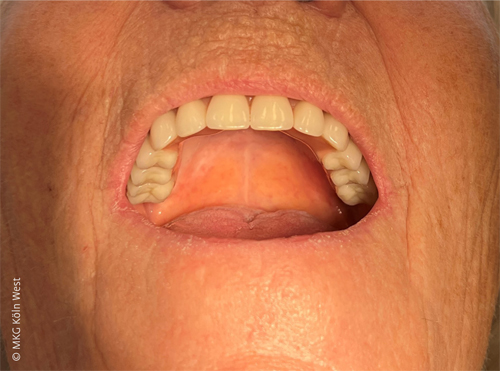

Der postoperative Verlauf war komplikationslos; insbesondere traten keine Wundheilungsstörungen oder Infektionen auf. Nach einer Einheilphase von etwa acht Wochen erhielt die Patientin ihre definitive prothetische Versorgung in Form einer auf den vier Pfeilern verschraubten Stegprothese.

Bei Nachkontrollen zeigte sich die Patientin hochzufrieden; sie berichtete über eine deutliche Verbesserung der Prothesenfunktion und Lebensqualität im Vergleich zur früheren konventionellen Totalprothese.

Intraoperativ konnte auf den sechs Pfeilern eine provisorische Interimsbrücke verschraubt werden, die eine sofortige provisorische Versorgung gewährleistete. Nach komplikationsfreier Wundheilung erhielt die Patientin acht Wochen postoperativ die definitive festsitzende Brückenversorgung im Oberkiefer.

Auch dieser Fall verlief erfolgreich; die Pfeilerimplantate oszillierten nicht und es traten keine Infektionen oder relevanten Expositionen des Gerüsts auf. Die Patientin konnte unmittelbar nach Versorgung beschwerdefrei mit normaler Kaufunktion essen und berichtete ebenfalls über eine klare Verbesserung gegenüber der vorherigen herausnehmbaren Versorgung.